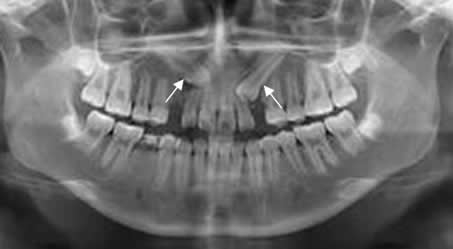

Fig 80. Dientes supernumerarios.

Ortopantografía. Dientes supernumerarios a nivel maxilar bilateral, en relación con los caninos.